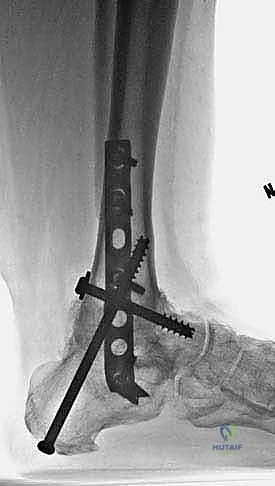

Follow-up (3 years)

The second screw, from the posterior tibia to the center of the talar head, lags the talar head to the prepared anterior distal tibial surface ( TECH FIG 11H ). An AP view of the foot confirms that the guide pin is in the center of the talar head.)())((()) ). An AP view of the foot confirms that the guide pin is in the center of the talar head.

Patient is ambulating comfortably without an assistive device; only a slight limp is appreciable.

She was issued a brace with a small lift but does not routinely wear it.

She is far more functional than preoperatively.

Obtain fluoroscopic confirmation of the construct in the AP, mortise, and lateral planes.

Radiographs demonstrate solid ankle and hindfoot fusion with near-physiologic alignment ( TECH FIG 12 ).

TECH FIG 12 • Final follow-up radiographs 3 years after procedure. A. AP view. B. Lateral view. A B